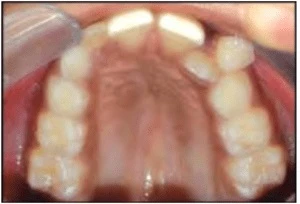

Các răng sau bị xoay chiếm nhiều khoảng hơn. Xoay lại các răng sau có thể giúp lấy lại khoảng. Khoảng trống được lấy lại khác nhau tùy thuộc vào răng liên quan và mức độ xoay. Với một góc xoay như nhau, răng cối lớn chiếm nhiều khoảng hơn so với răng cối nhỏ; trong khi răng trước chiếm ít khoảng hơn.

Hình 6A. Răng sau xoay chiếm nhiều khoảng trống hơn